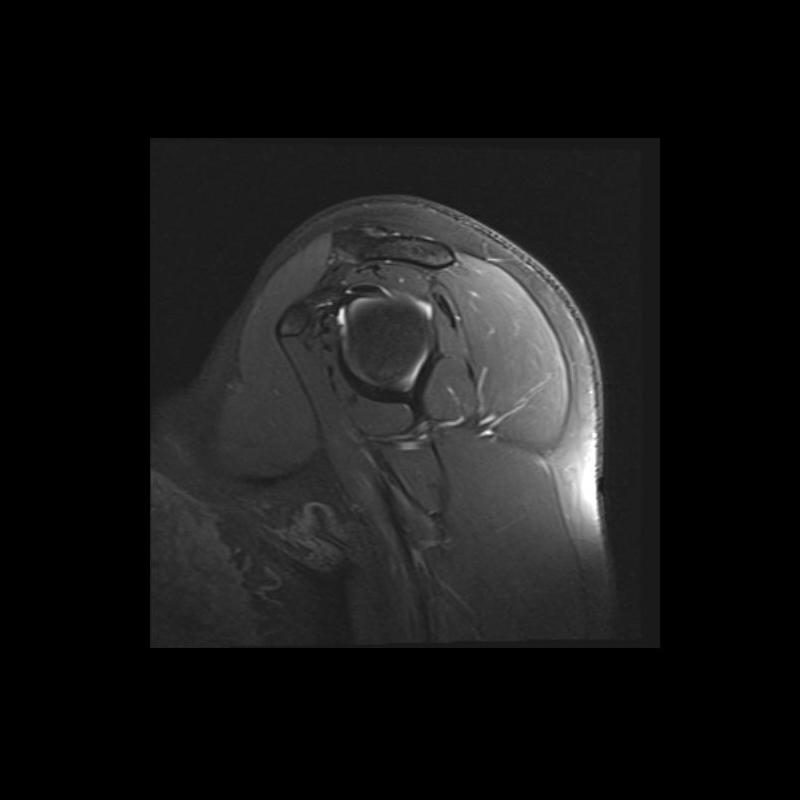

Shoulder MRI Anatomy